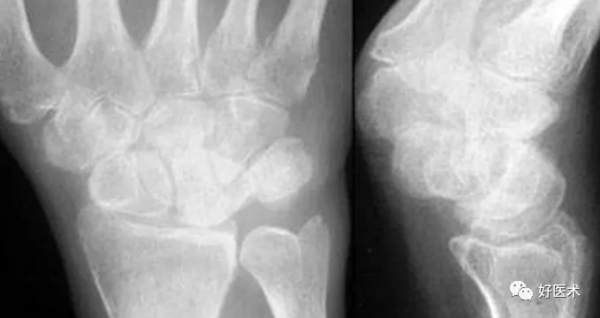

成人期腕關節正側位及舟骨蝶位片

1.舟骨 2.月骨 3.三角骨 4.豆狀骨 5.大多角骨 6.小多角骨 7.頭狀骨 8.鉤骨 9.橈骨莖突 10.尺骨莖突 11.第一掌骨基部

12.舟骨結節 黑箭:舟骨腰部 白箭:舟骨滋養血管影